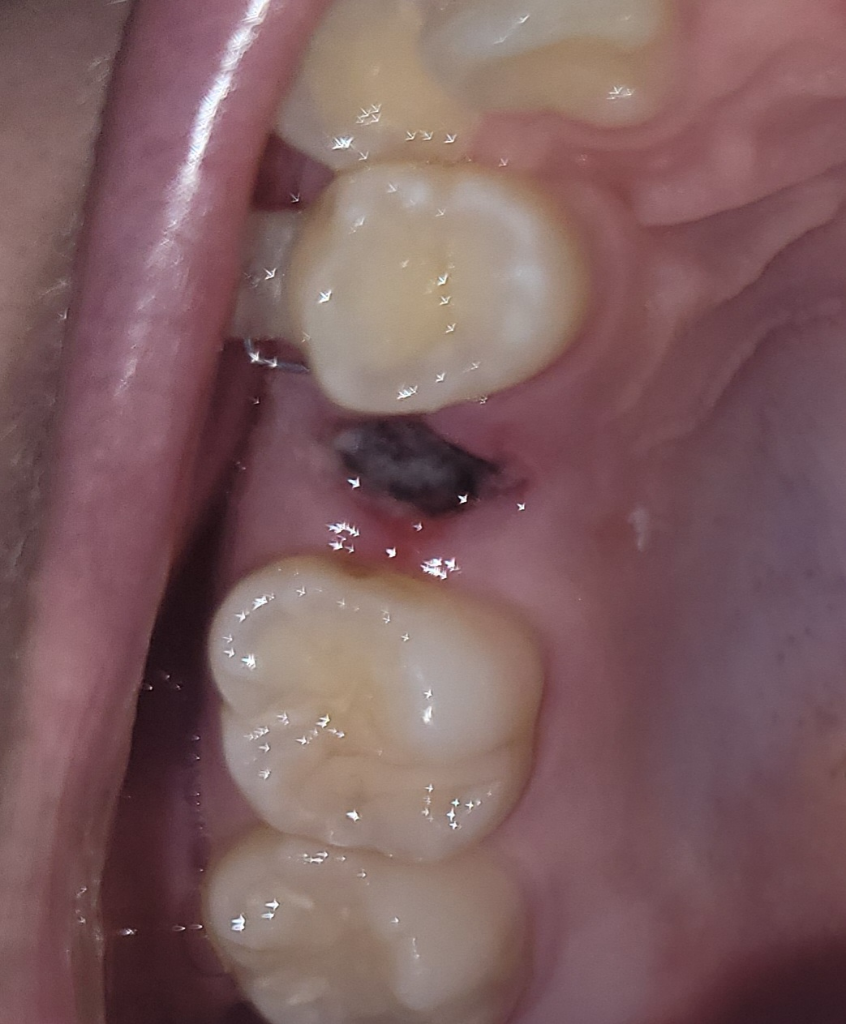

치아 발치 후 잘 아물고 있는지 확인해주실 수 있나요?

상악 작은어금니 발치 후 55시간 정도 지난 상태인데 잘 아물고 있는지 확인 부탁드립니다

겉부분에 곰팡이처럼 생긴게 있는데 저게 뭔지, 안 좋은건지 궁금합니다 입을 계속 헹궈도 사라지지 않던데 건드리지 않는게 좋을까요?

• 1번 째 사진

하얗게 막이 생기는 것은 낫기 위한 과정입니다. 일부러 건드리지 마시고 주의사항 지켜주면 됩니다.

사진상으로 보면 잘 아물고 있는거 같습니다. 일주일정도는 최대한 발치한곳에 자극이 가지 않도록 해주세요.

사진으로만 봤을 경우에는 혈병을 잘 형성되고 아물고 있는 것으로 보입니다.

발치를 한 부위를 자극하게 되면 출혈이 되고 치유가 늦어질 수 있기 때문에 발치를한 부위는 건들지 않는 것이 좋습니다.

잘아물고 있는 것으로 보이며, 혈병이 생기고 있는 것으로 일부러 떼어나거나 하지 말고 그대로 두시면 됩니다.